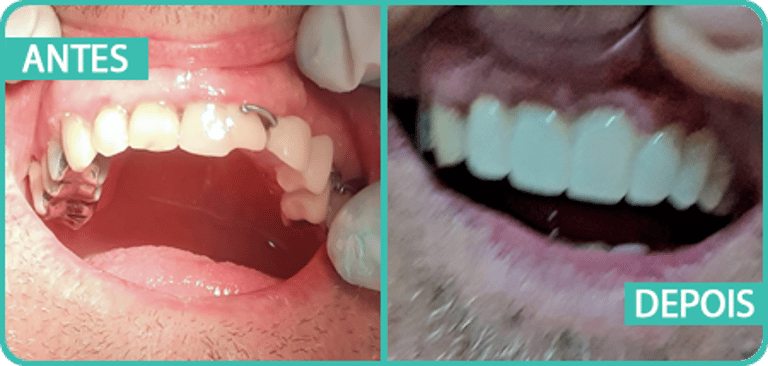

Tratamentos realizados

Sorrisos transformados. Confiança renovada.